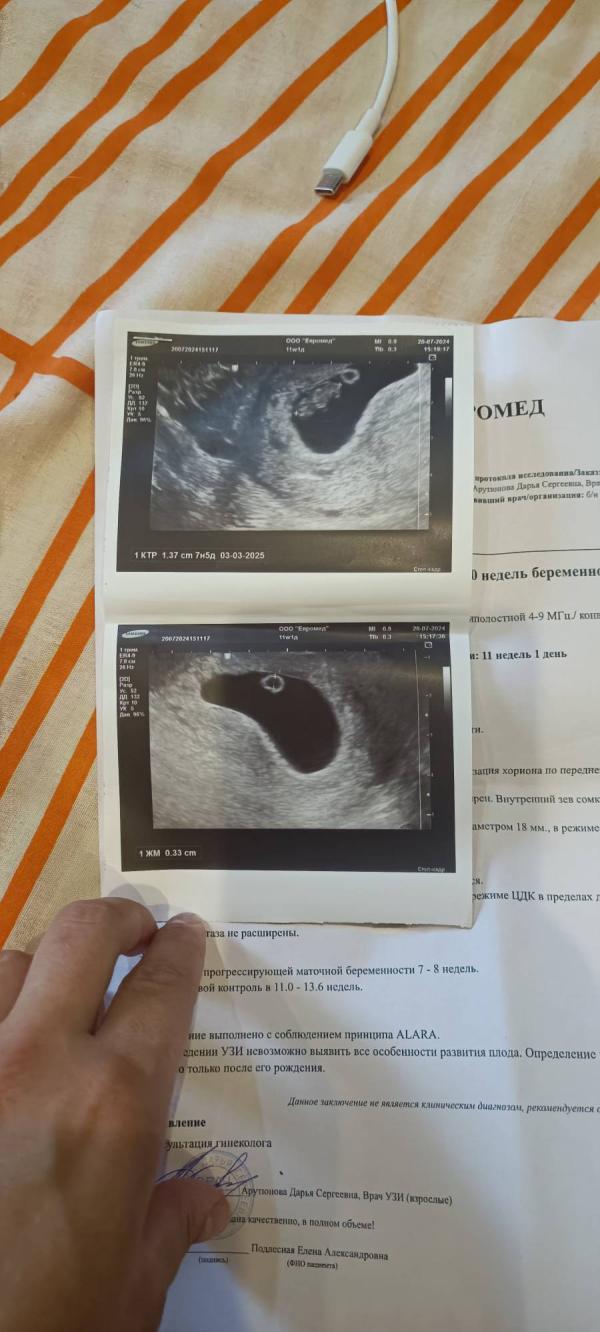

За 11 дней вырос с 4.3мм до 13,7мм